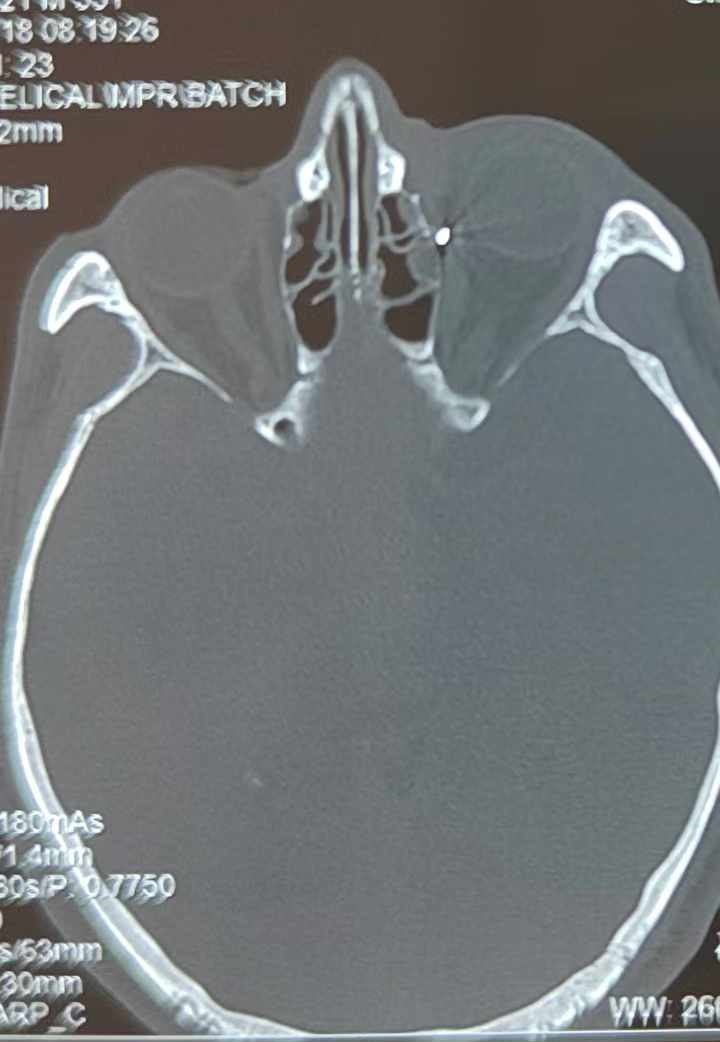

從CT報告中可以看出,高先生眼內(nèi)的異物不是很大,但位于眼窩深處,緊鄰鼻骨,從CT影像判斷應(yīng)該是金屬或合金異物。一般臨床上遇到這樣的情況,醫(yī)生會建議“保守觀察”,若異物傷及神經(jīng)、發(fā)生炎癥感染等,則需到條件較好、有眼眶病和眼外傷專業(yè)醫(yī)師的醫(yī)院進(jìn)行二期眶內(nèi)異物取出術(shù)(2021年《中國眼眶異物診斷和治療專家共識》)。

李海波博士介紹,眶內(nèi)異物想要通過手術(shù)取出,難度很大,一是因為位置隱匿,無法實現(xiàn)可視化操作;二是如果是磁性異物,現(xiàn)有手術(shù)工具磁性強度有限,很難吸出這么深的異物;三是可操作空間極為狹小,眶周軟組織多,異物周邊包裹緊密,像高先生這種情況,異物周邊還有很多神經(jīng)、血管,手術(shù)難度更高。